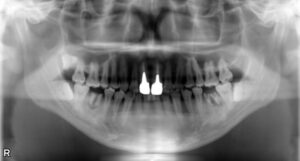

下顎大臼歯1本欠損症例

BEFORE AFTER 33歳女性/下顎1本欠損/インプラント埋込手術 【治療内容】 左下第一大臼歯がむし歯の進行が原…